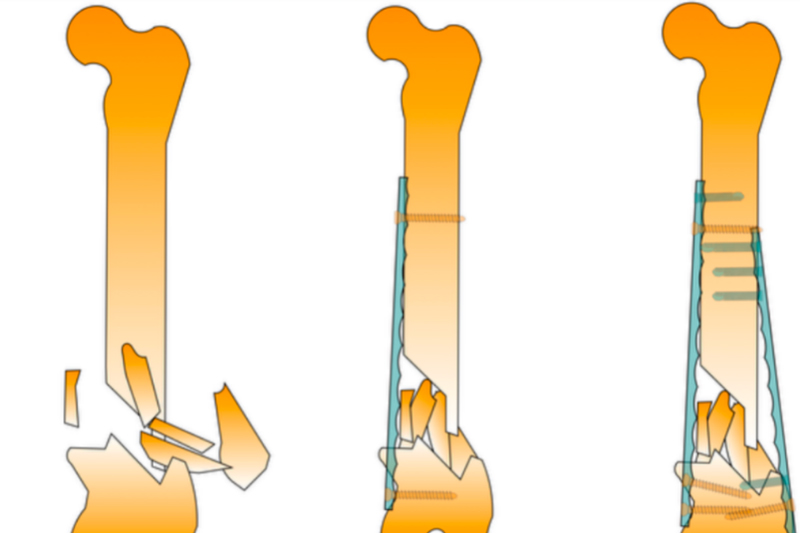

Veterinary spinal pedicle screws

The hemilaminectomy site was redefined preoperatively based on plain X-rays (Figures 1 and 2). Surgical approach: A single incision of the skin and subcutaneous fat was made parallel to the dorsal midline, offset 1 cm (Figure 3). The lumbar multifidus muscle attached to each spinous process was exposed using a scalpel. The lumbar multifidus muscle was then bluntly dissected from the lamina using a periosteal elevator until it reached the facet articular processes (Figure 4). One or two articular processes were dissected in sequence, anterior and posterior to the affected area, and the surrounding tissue was completely separated from the bone to fully expose the articular processes. A rongeur was used to create a bite mark in the lamina anterior and posterior to the affected area, with repeated manipulations to deepen the mark. When cancellous bone was visible (Figure 6) and the dura mater was visualized, the rongeur was discontinued and replaced with a nucleus pulposus forceps, carefully removing the bone from the lamina to expose the medullary cavity. The rongeur and nucleus pulposus forceps were then used alternately to remove the affected articular processes, further exposing the medullary cavity (Figures 7 and 8). After the main surgery, the wound is irrigated, blood clots and bone fragments are removed, a fat pad is placed on the exposed medullary cavity, the lumbar muscles are repositioned, and the dorsal fascia is sutured. The skin tissue is closed routinely.